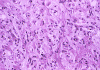

Histopathology: On histologic examination, the cortex lesion (C-L in Panel A) appear fibrous and vascular. It is well demarcated from the white matter (W in Panel A). The cortical lesion respects the grey-white junction and the interface is smooth. These features are better appreciated on Masson's trichrome stain. While one side of the gyrus is replaced by the lesion (C-L in Panel E), normal cortex is present on the other side of the gyrus (C-N in Panel E). White matter (W in Panel E) and the normal cortex (C-N in Panel E) carry a pink hue on Masson's trichrome.he fibrous lesion (C-L in Panel E) does not carry much of this pink hue.  The lesion essentially follow the shape of the gyrus with some cortical thickening (Panel F). On higher magnification, the cortical lesion is highly vascular (Panel B, C, and G). In between the fibrous vascular component, there are entrapped islands of cortical tissue (Panel D, H, and I ). There is a general lack of pleomorphism and mitotic activities in the lesion.

Histologically, the salient feature is a disorganized lesion featured by perivascular meningothelial cells intermingled with a fine, rich vascular network. Although each lesion is unique, increased cortical vascularity and perivascular cellular proliferation are constant findings. Irregularly branched blood vessels extending into the gray matter from the meningeal surface are surrounded by a concentric arrangement of proliferating spindle-formed cells .The overall structure can occur as nodules, whorls, or bands. Islands of cortical tissue with gliosis are often trapped within the lesion. The ratio between meningothelial component and vascular component varies substantially. There are lesions predominantly composed of vascular component or meningothelial component 3. A schwannian component can also occur. There are also cortical meningovascular fibroblastic proliferation and leptomeningeal calcifications that range from faint psammomatous calcification to dense osteoid. Residual neurons entrapped within the lesion may contain neurofibrillary tangles with ultrastructural and immunostaining properties identical to those seen in Alzheimer's disease but there is no deposition of amyloid Ab.